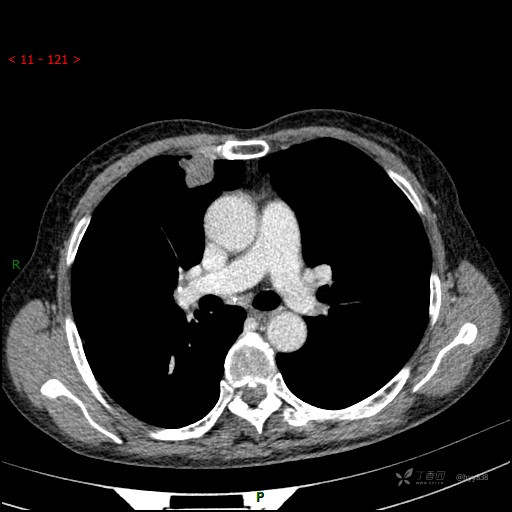

增强动脉期